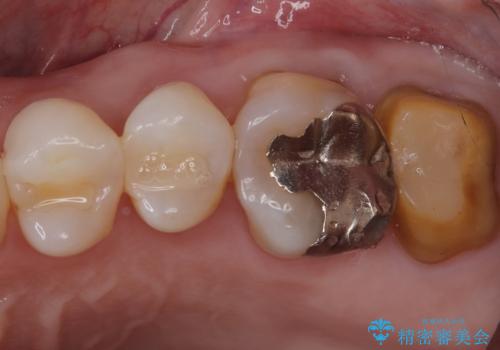

- 主訴:詰め物と歯の奥が側の境目に物がいつも溜まってしまう

保険適応のメタルインレーと歯質との間に不適合な箇所を認め、補綴物のやり替えでの治療となりました。インレーからクラウンへ補綴物の形態を変更し、素材は清掃性・適合性・審美性の点からセラミッククラウンでのやり替となりました。

レントゲン上にて、左上6番遠心にインレーと歯質の不適合を認めます。